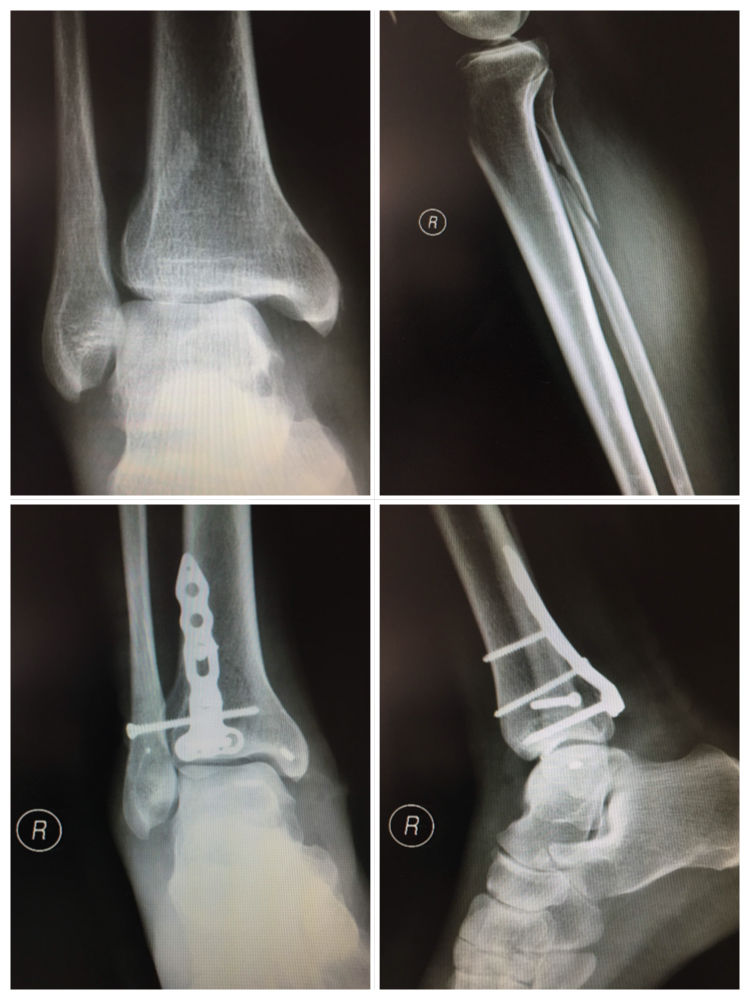

足踝创伤类手术是我学习交流的主战场。后踝骨折经外踝骨折掀起暴露复位的方法,后踝骨折需要板钉固定的情况,下胫腓前联合修复的方法,跟骨骨折撬拨复位要点,Pilon骨折复位的顺序,陈旧骨折复位的技巧等等,每一台手术都是一次难得的学习机会,受益匪浅。